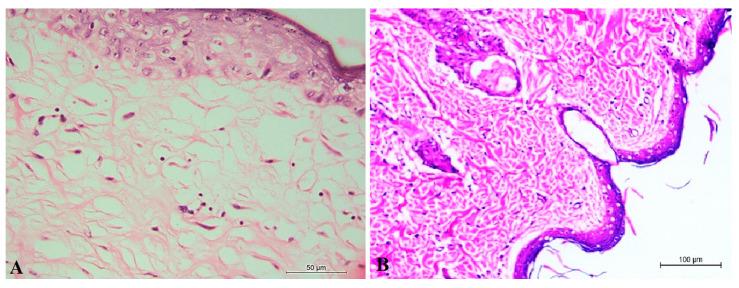

Cancer is one of the most important causes of death worldwide. Several studies have shown the efficacy of apricot kernel seed as a cancer therapy due to the presence of amygdalin. These studies have demonstrated amygdalin's cytotoxicity, antioxidant activity, and apoptosis in vitro using human cancer cell lines. However, no studies have demonstrated their cancer activity in vivo. The aim of this study is to develop an amygdalin-loaded niosomes (ALN) gel formulation as a drug delivery system in order to investigate the selectivity, efficacy, and toxicity of amygdalin as a cancer therapy in vivo using the 7,12-dimethylbenz (a) anthracene (DMBA) carcinoma rat model. Based on pre-formulation studies, the ALN formulation composed of Tween 60: cholesterol: dihexadecyl phosphate in a molar ratio of 1:2:0.1 was chosen as an optimum formulation because it has a percent of EE of 66.52% with a particle size of 269.3 nm and a reflux of 3.54 µg.cm.h. The ALN gel formulation was integrated into carbopol gel to be evaluated in vivo. Compared to DMBA control, treatment with ALN gel showed a reduction in the carcinoma volume and in the hyperplasia of the epidermis with no signs of edema. In conclusion, the ALN gel formulation could be an efficient cancer therapy.

癌症是全球最重要的死因之一。多项研究表明,由于苦杏仁苷的存在,杏仁核种子作为一种癌症治疗方法具有疗效。这些研究使用人类癌细胞系在体外证明了苦杏仁苷的细胞毒性、抗氧化活性和凋亡作用。然而,尚无研究在体内证明其抗癌活性。本研究的目的是开发一种载有苦杏仁苷的非离子表面活性剂囊泡(ALN)凝胶制剂作为药物递送系统,以便使用7,12-二甲基苯并(a)蒽(DMBA)诱导的大鼠癌模型在体内研究苦杏仁苷作为癌症治疗的选择性、疗效和毒性。基于处方前研究,选择由吐温60:胆固醇:磷酸二己酯按1:2:0.1的摩尔比组成的ALN制剂作为最佳制剂,因为它的包封率为66.52%,粒径为269.3 nm,回流率为3.54 µg.cm.h。将ALN凝胶制剂整合到卡波姆凝胶中进行体内评估。与DMBA对照组相比,用ALN凝胶治疗显示癌体积减小,表皮增生减少,且无水肿迹象。总之,ALN凝胶制剂可能是一种有效的癌症治疗方法。